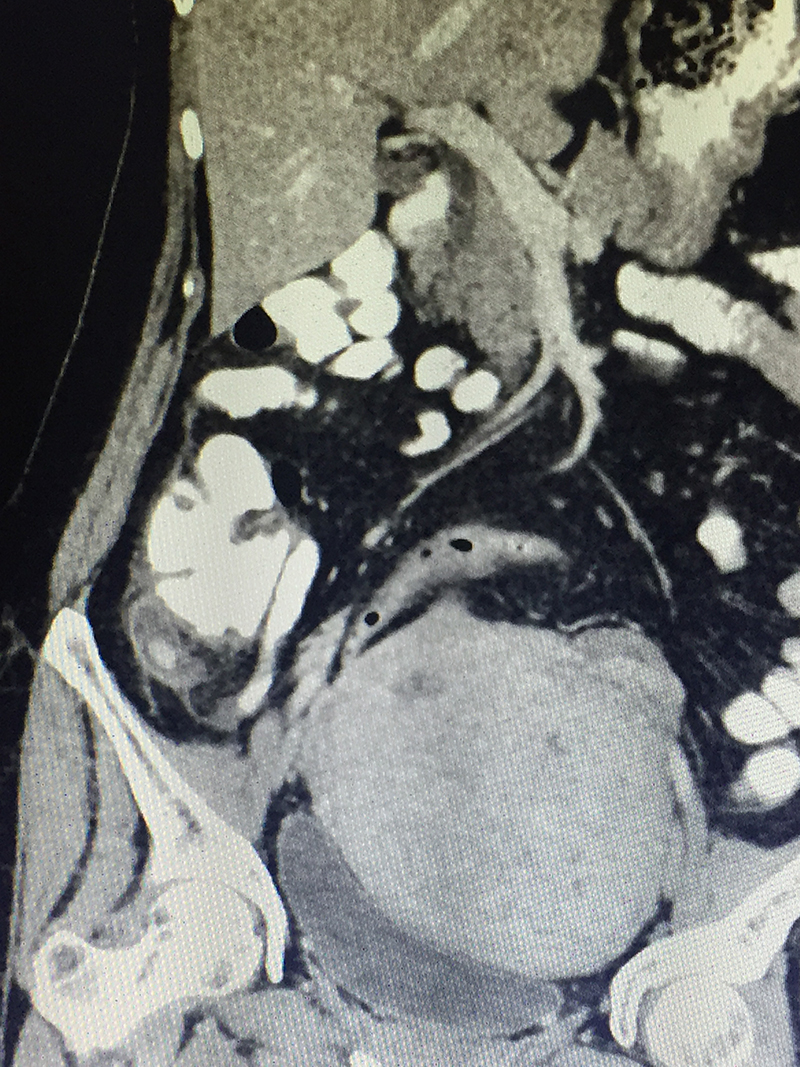

50 year old lady with acute abdominal pain in the right lower abdomen, vomiting and fever was diagnosed with acute appendicitis. Preliminary blood investigations & ultrasonography corroborated the diagnosis. A CT scan of the abdomen and pelvis was done to confirm the diagnosis & look for complications like perforation & abscess. An acute appendicitis with localized perforation & infected fluid collection was observed. She also had a large fibroid in her uterus. As is our policy (most acute appendicitis patients are treated by laparoscopic surgery), patient underwent a laparoscopy. At the time of laparoscopy, a perforated gangrenous appendix was found with a large walled off pus collection in the abdomen. The huge fibroid made the surgery difficult since it kept on coming in the line of surgery. However the appendicectomy was successfully completed laparoscopically and patient was discharged on 4th postoperative day. Due to the existing infection, a hysterectomy for the fibroid was not performed at the same time. It was done later after few months.

When there is a clinical suspicion of acute appendicitis, he / she is subjected to blood (CBC / CRP) investigations and imaging study (Ultrasonography). Severe colitis / enteritis / mesenteric lymphadenitis, ileal perforation, intestinal tuberculosis, inflammatory bowel disease, colonic diverticulitis, pericolic appendagitis, Meckel’s diverticulum etcetera can have present with similar symptoms and signs. Some of these diseases can be managed with medicines alone. Hence a CT scan of abdomen and pelvis with oral and intravenous contrast is advised before any surgery is planned for appendicitis. CT scan not only confirms diagnoses, but also reveals complications like perforation, abscess etcetera or an alternative diagnosis or associated malignancy (as in elderly patients).